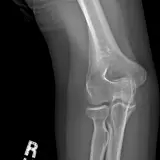

MSK Radiographs

Peds Radiographs